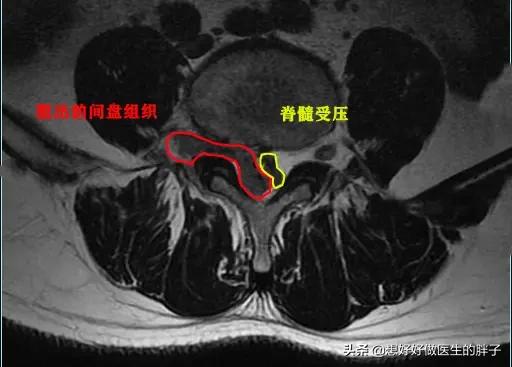

这是本人的一个患者,他本身就有腰椎间盘突出,但是不重,后来由于错误的搬动重物以后诱发剧烈的腰痛,不能正常睡觉,只能坐着才能减轻腰部以及肢体的疼痛、和麻木,后来给与其进行了椎管麻醉以后,才能平卧进行核磁,当时显示椎间盘突出属于侧方突出,压迫到了神经,单纯的看检查肯定是手术适应症。

但是给予患者进行了椎管麻醉以后,患者的疼痛明显减轻了,连续观察了5~10天,患者已经可以正常的行走了,而且一个劲的吵着要上班,后来经过劝说才复查了核磁,结果发现患者的椎间盘突出已经达到了脱出的程度,复杂的核磁上,我们看脱出的髓核已经导致了椎管出现了明显的狭窄,如此严重的情况单纯看片子是手术适应症,但是患者却没有表现出来任何需要手术的症状,所以还是保守治疗了,最近一次随访是一个月前……患者很好!